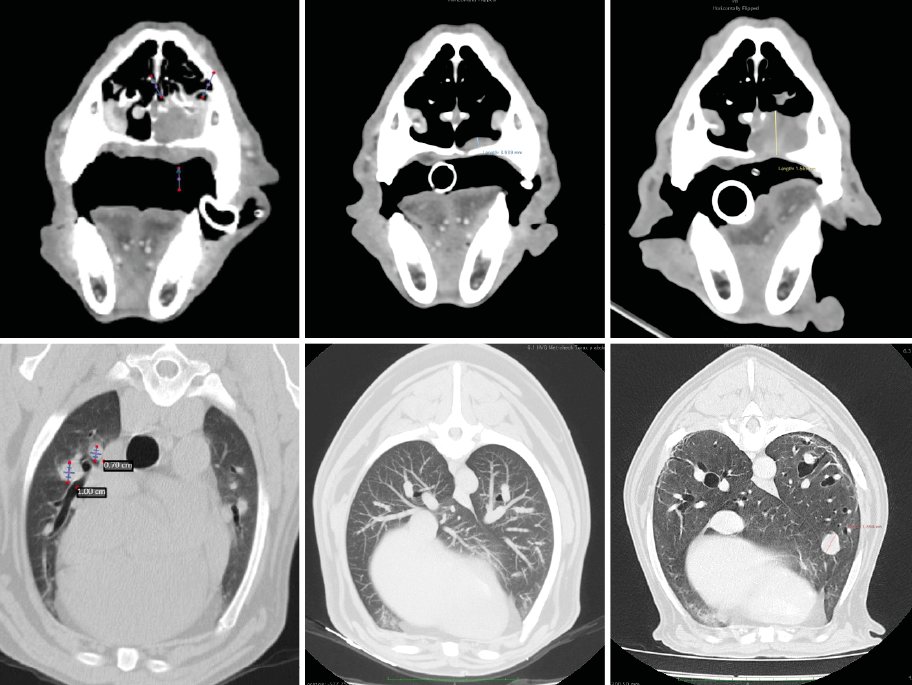

A los 18 meses del diagnóstico, los cuidadores refieren la aparición de hifema y exoftalmia en el ojo derecho, lo que sugiere metástasis, además de una masa perianal compatible con neoplasia indiferenciada (posible melanoma amelanótico). En el estudio de TC se documenta una respuesta completa de la lesión primaria y metástasis nodales y una remisión casi completa de las metástasis pulmonares (lesiones milimétricas equívocas) (imagen 1). Se realiza la resección de la masa perianal, pero los cuidadores rechazan la enucleación.

A los 28 meses se realiza un TC de re-estadiaje antes de considerar el segundo protocolo de radioterapia, donde se documenta una progresión objetiva de la masa oral y ligera progresión de la metástasis pulmonar (imagen 1).